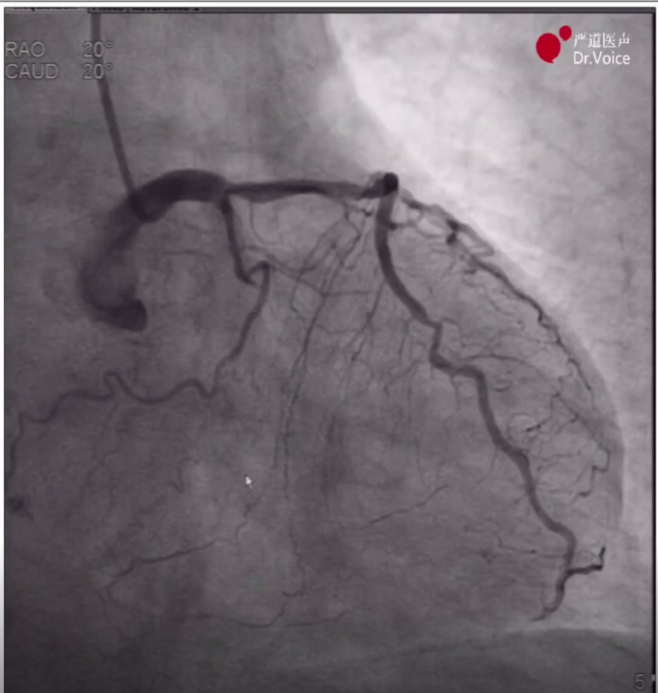

1、术前造影显示LAD弥漫病变、中段完全闭塞,LCX原支架血流通畅,RCA血管纤细、中段完全闭塞,远段侧枝循环形成。

LAD造影图像

RCA造影图像